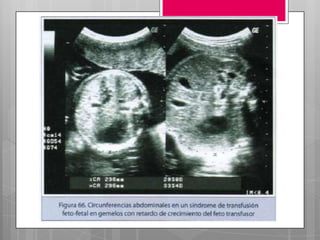

 Afecta el 30% mas habitual en gemelos

 Se crea un flujo global de un gemelo a otro,

dando lugar un feto transfusor y uno transfundido.

 El gemelo donante: retraso del crecimiento,

anemia, hipovolemia. Oligohidramnios.

 El gemelo receptor: hipervolemia, HTA, ICC.

polihidramnios.

Patología asociada: Síndrome detransfusión feto- fetal.  Afecta el 30% mas habitual en gemelos monocigotos.  A medida que avanza una gestación univitelina, puede producirse distintas anastomosis vasculares entre los fetos.  Se crea un flujo global de un gemelo a otro, dando lugar un feto transfusor y uno transfundido.  El gemelo donante: retraso del crecimiento, anemia, hipovolemia. Oligohidramnios.  El gemelo receptor: hipervolemia, HTA, ICC. polihidramnios.